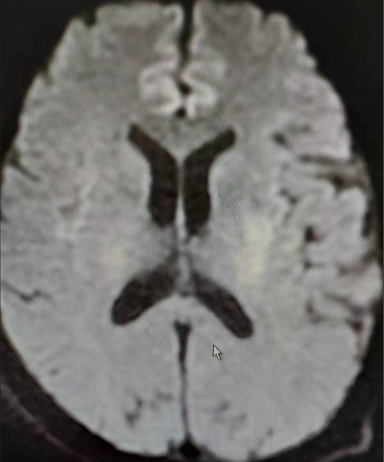

在溶栓治疗1个小时后,患者口齿逐渐清楚,右侧肢体肌力逐渐恢复;3个小时后,及时行MRI-头部扫描。扫描结果显示:左侧脑室体部旁、左侧基底节区急性缺血缺氧脑损伤,左侧大脑中动脉M3段起始处局部变窄。扫描结果坚定了医护人员的信心。在溶栓治疗24小时后,再次复查颅脑CT,并将结果与溶栓3+小时颅脑MRI片进行了比较,显示:颅脑左侧基底节豆状核提示脑梗塞。针对对比结果,继续跟进后期治疗方案。经过系列治疗,患者右侧肢体肌力已基本恢复,约Ⅴ-级,无言语障碍,无头晕、头痛等不适,转入内一科普通病房观察治疗。